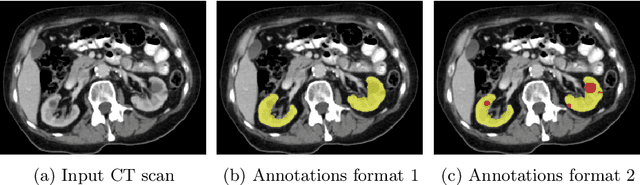

Abstract:Kidney abnormality segmentation has important potential to enhance the clinical workflow, especially in settings requiring quantitative assessments. Kidney volume could serve as an important biomarker for renal diseases, with changes in volume correlating directly with kidney function. Currently, clinical practice often relies on subjective visual assessment for evaluating kidney size and abnormalities, including tumors and cysts, which are typically staged based on diameter, volume, and anatomical location. To support a more objective and reproducible approach, this research aims to develop a robust, thoroughly validated kidney abnormality segmentation algorithm, made publicly available for clinical and research use. We employ publicly available training datasets and leverage the state-of-the-art medical image segmentation framework nnU-Net. Validation is conducted using both proprietary and public test datasets, with segmentation performance quantified by Dice coefficient and the 95th percentile Hausdorff distance. Furthermore, we analyze robustness across subgroups based on patient sex, age, CT contrast phases, and tumor histologic subtypes. Our findings demonstrate that our segmentation algorithm, trained exclusively on publicly available data, generalizes effectively to external test sets and outperforms existing state-of-the-art models across all tested datasets. Subgroup analyses reveal consistent high performance, indicating strong robustness and reliability. The developed algorithm and associated code are publicly accessible at https://github.com/DIAGNijmegen/oncology-kidney-abnormality-segmentation.

Abstract:In this study, we introduce a deep learning approach for segmenting kidney parenchyma and kidney abnormalities to support clinicians in identifying and quantifying renal abnormalities such as cysts, lesions, masses, metastases, and primary tumors. Our end-to-end segmentation method was trained on 215 contrast-enhanced thoracic-abdominal CT scans, with half of these scans containing one or more abnormalities. We began by implementing our own version of the original 3D U-Net network and incorporated four additional components: an end-to-end multi-resolution approach, a set of task-specific data augmentations, a modified loss function using top-$k$, and spatial dropout. Furthermore, we devised a tailored post-processing strategy. Ablation studies demonstrated that each of the four modifications enhanced kidney abnormality segmentation performance, while three out of four improved kidney parenchyma segmentation. Subsequently, we trained the nnUNet framework on our dataset. By ensembling the optimized 3D U-Net and the nnUNet with our specialized post-processing, we achieved marginally superior results. Our best-performing model attained Dice scores of 0.965 and 0.947 for segmenting kidney parenchyma in two test sets (20 scans without abnormalities and 30 with abnormalities), outperforming an independent human observer who scored 0.944 and 0.925, respectively. In segmenting kidney abnormalities within the 30 test scans containing them, the top-performing method achieved a Dice score of 0.585, while an independent second human observer reached a score of 0.664, suggesting potential for further improvement in computerized methods. All training data is available to the research community under a CC-BY 4.0 license on https://doi.org/10.5281/zenodo.8014289